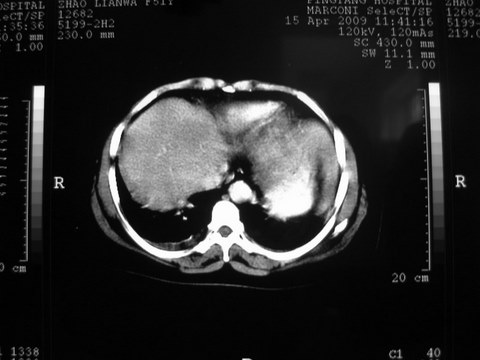

患者 女 51岁 两天前感觉上腹疼,无明显诱因,b超示肝右叶囊实性占位,边缘清楚,其内回声不均匀,ct增强如图,大家看看是什么 ,病人一年前及两月前b超检查只是提示胆囊炎

外院术后,证实肝癌合并出血

特点:1,病灶发展迅速,(2月前正常)[br] 2,囊实性,且并边界清晰光滑,呈右后叶赘生性。囊性区无强化,实性部分较多轻度强化,边界欠清。考虑囊腺癌或囊腺瘤。

出病理 中分化肝细胞癌合并出血